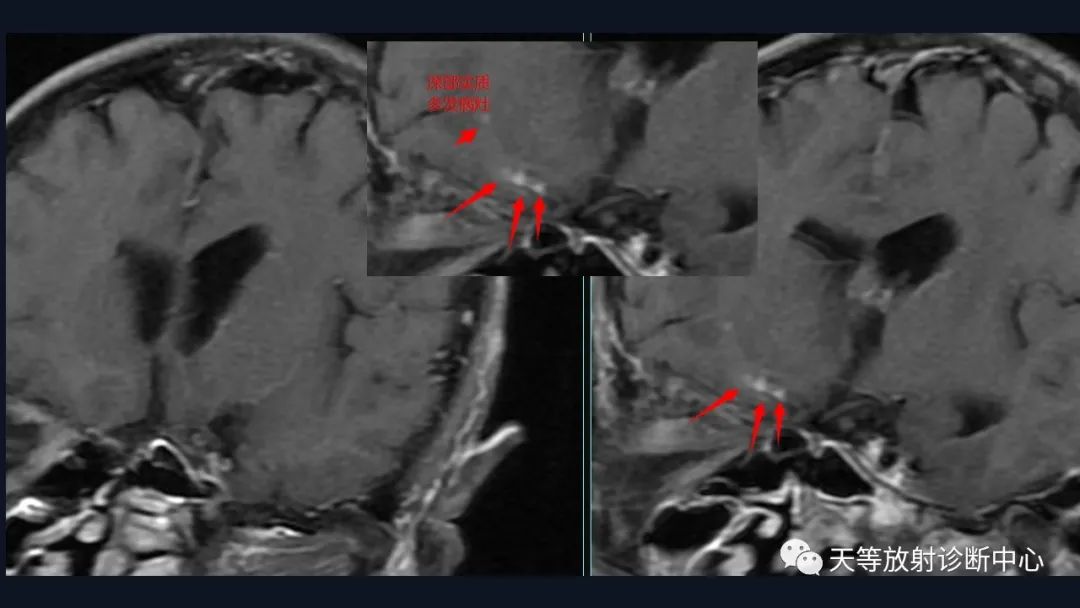

本病例影像学特点:

脑内占位的特点:

1、刀切征

2、凹陷征或肚脐凹征

3、尖角征

4、多发

5、DWI呈稍高信号

6、形态上怪异

6、NAA及Cho减低,出现导致LL峰。

结合颈部、胸廓入口区及腋窝多发淋巴结肿大并相互融合。

综合考虑淋巴瘤